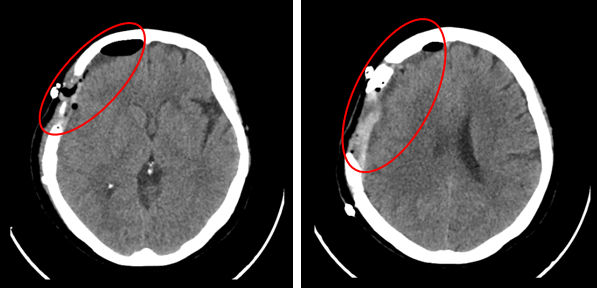

Hình 1: Hình ảnh MRI sọ não có tiêm thuốc đối quang từ: Ngoài trục vùng trán đỉnh phải và trong xương trán, đỉnh phải có khối tổn thương kích thước 68x36 mm, bờ đều, ranh giới rõ, sau tiêm ngấm thuốc mạnh đồng nhất, đẩy lồi da và phần mềm dưới da, đè đẩy nhu mô não nhưng không gây phù não.

Hình 2: Hình ảnh chụp cắt lớp vi tính sọ não không tiêm thuốc cản quang: Khối u đã được phẫu thuật, hình ảnh tụ dịch-máu-khí dưới màng cứng vùng trán phải.

Mô tả trong quá trình phẫu thuật: Khối u màng não trán đỉnh phải 6x3 cm, mật độ mềm, ranh giới rõ, khối u xâm lấn màng cứng, xoang tĩnh mạch, ăn khuyết xương sọ một diện 3x5 cm.